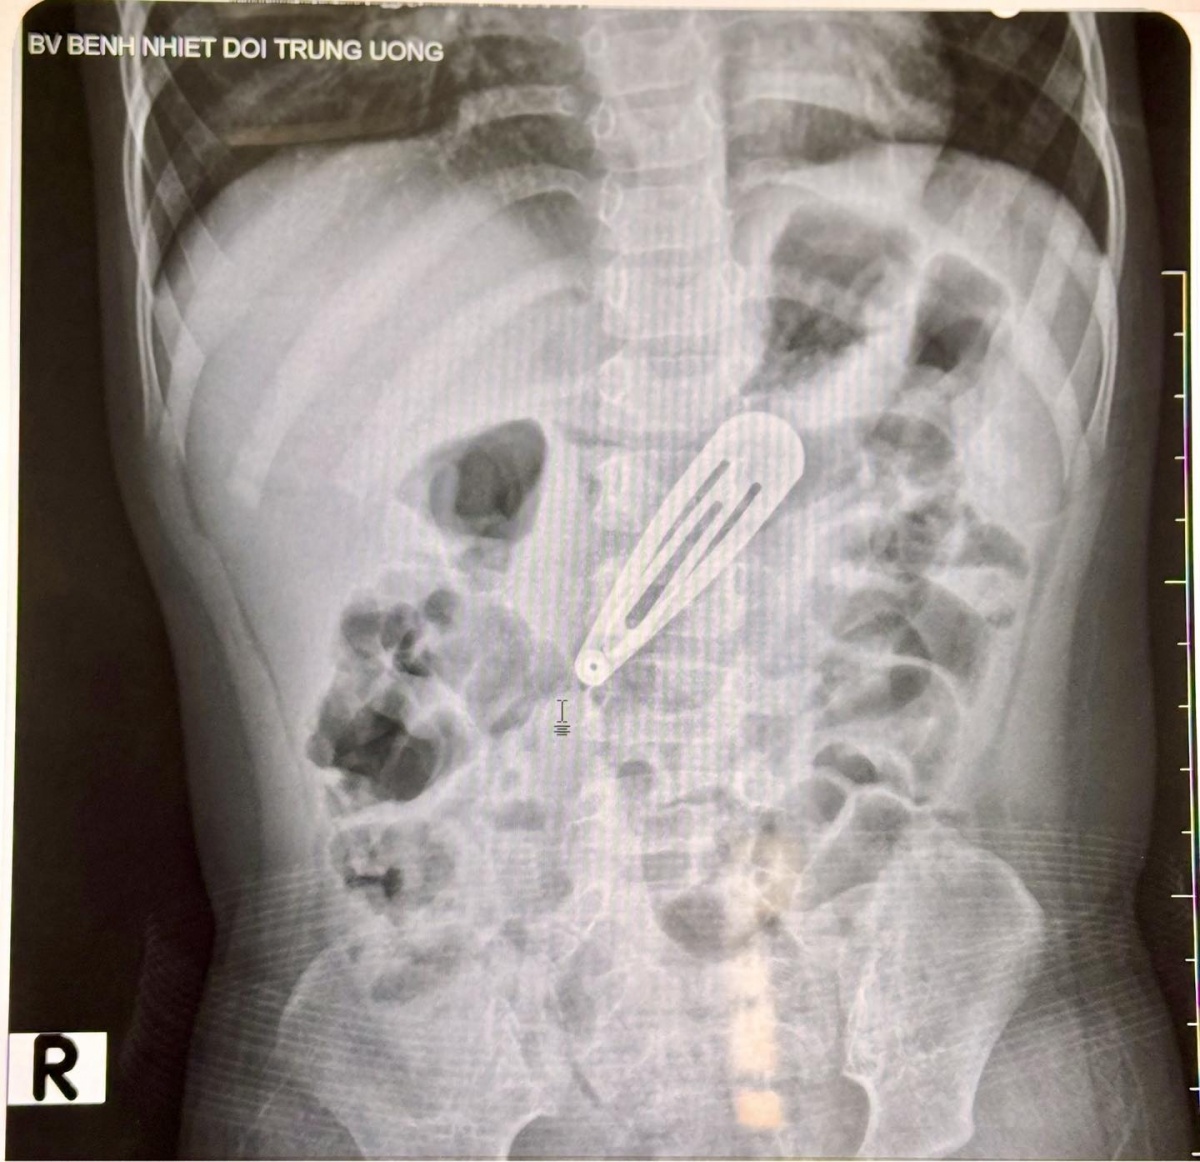

Mới đây, Bệnh viện Bệnh Nhiệt đới Trung ương tiếp nhận một bé gái N.T.P.T (21 tháng tuổi, trú tại Hà Nội) trong tình trạng đang nuốt phải một chiếc kẹp tóc kim loại dài khoảng 5cm.

Theo lời kể của người nhà, trong lúc chơi cùng chị gái (8 tuổi), bé vô tình cầm chiếc kẹp tóc và cho vào miệng. Khi phát hiện sự việc, người chị cố gắng lấy dị vật ra nhưng không thành công, chiếc kẹp đã trôi sâu vào họng và không thể quan sát hay gắp ra bằng tay. Bé xuất hiện biểu hiện ho nhẹ, nôn sữa.

Sau khi thăm khám lâm sàng và chụp X-quang bụng, các bác sĩ ghi nhận hình ảnh một dị vật kim loại nằm trong ổ bụng, tương ứng vị trí dạ dày của bé. Bé nhanh chóng được chuyển sang Trung tâm Nội soi tiêu hóa và Thăm dò chức năng để tiến hành nội soi can thiệp lấy dị vật ra ngoài.

Hình ảnh chụp X - quang của bé gái, nhìn rõ chiếc kẹp tóc nằm trong dạ dày. (Ảnh: BV Bệnh Nhiệt đới Trung ương)